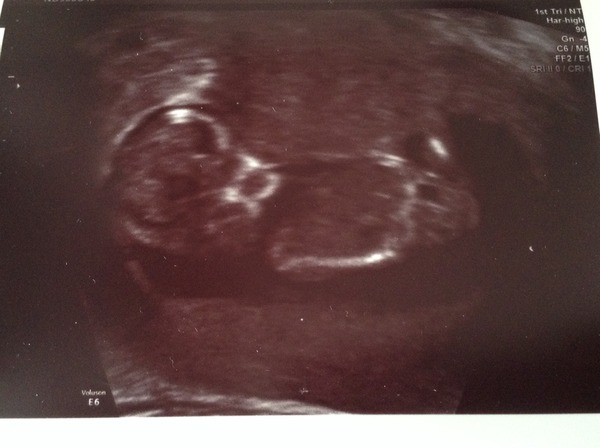

Bugaboom · 02/07/2014 18:35

Lovely to hear all the scan news. My scan is also tomorrow.

12+6

Mini I think girl based on skull theory!

fancyacupoftea · 02/07/2014 18:37

Very different to the skull of my blob!

I had a go at the skull theory game but I was a bit pants at it and my scan pic isn't that clear as mini lamp was not keen on lying still!

Lady oooh a great scan pic for doing the skull theory!! Congrats too!

I think baby is looking straight at the screen, that's why there isn't a great profile in the photo and you can see eye and jaw shadows.

I am seriously doubting my nub skills but I'm going to say girl

Ooh, mini and lady I think both girls! (Bear in mind that I have literally no idea what I'm talking about. Wink)